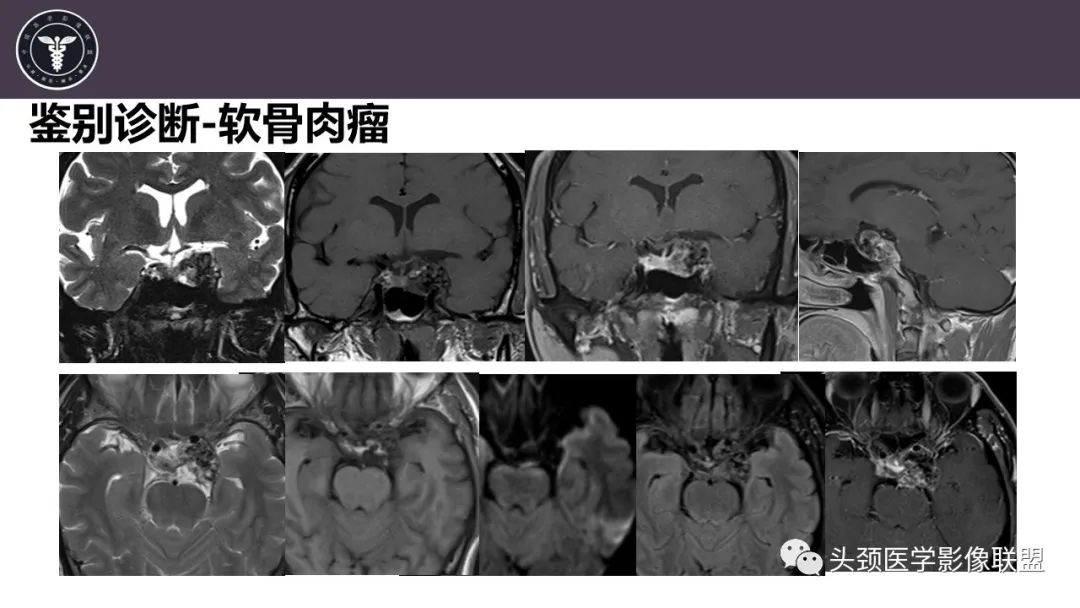

病例2

【病例】斜坡区骨巨细胞瘤 VS 脊索瘤-16